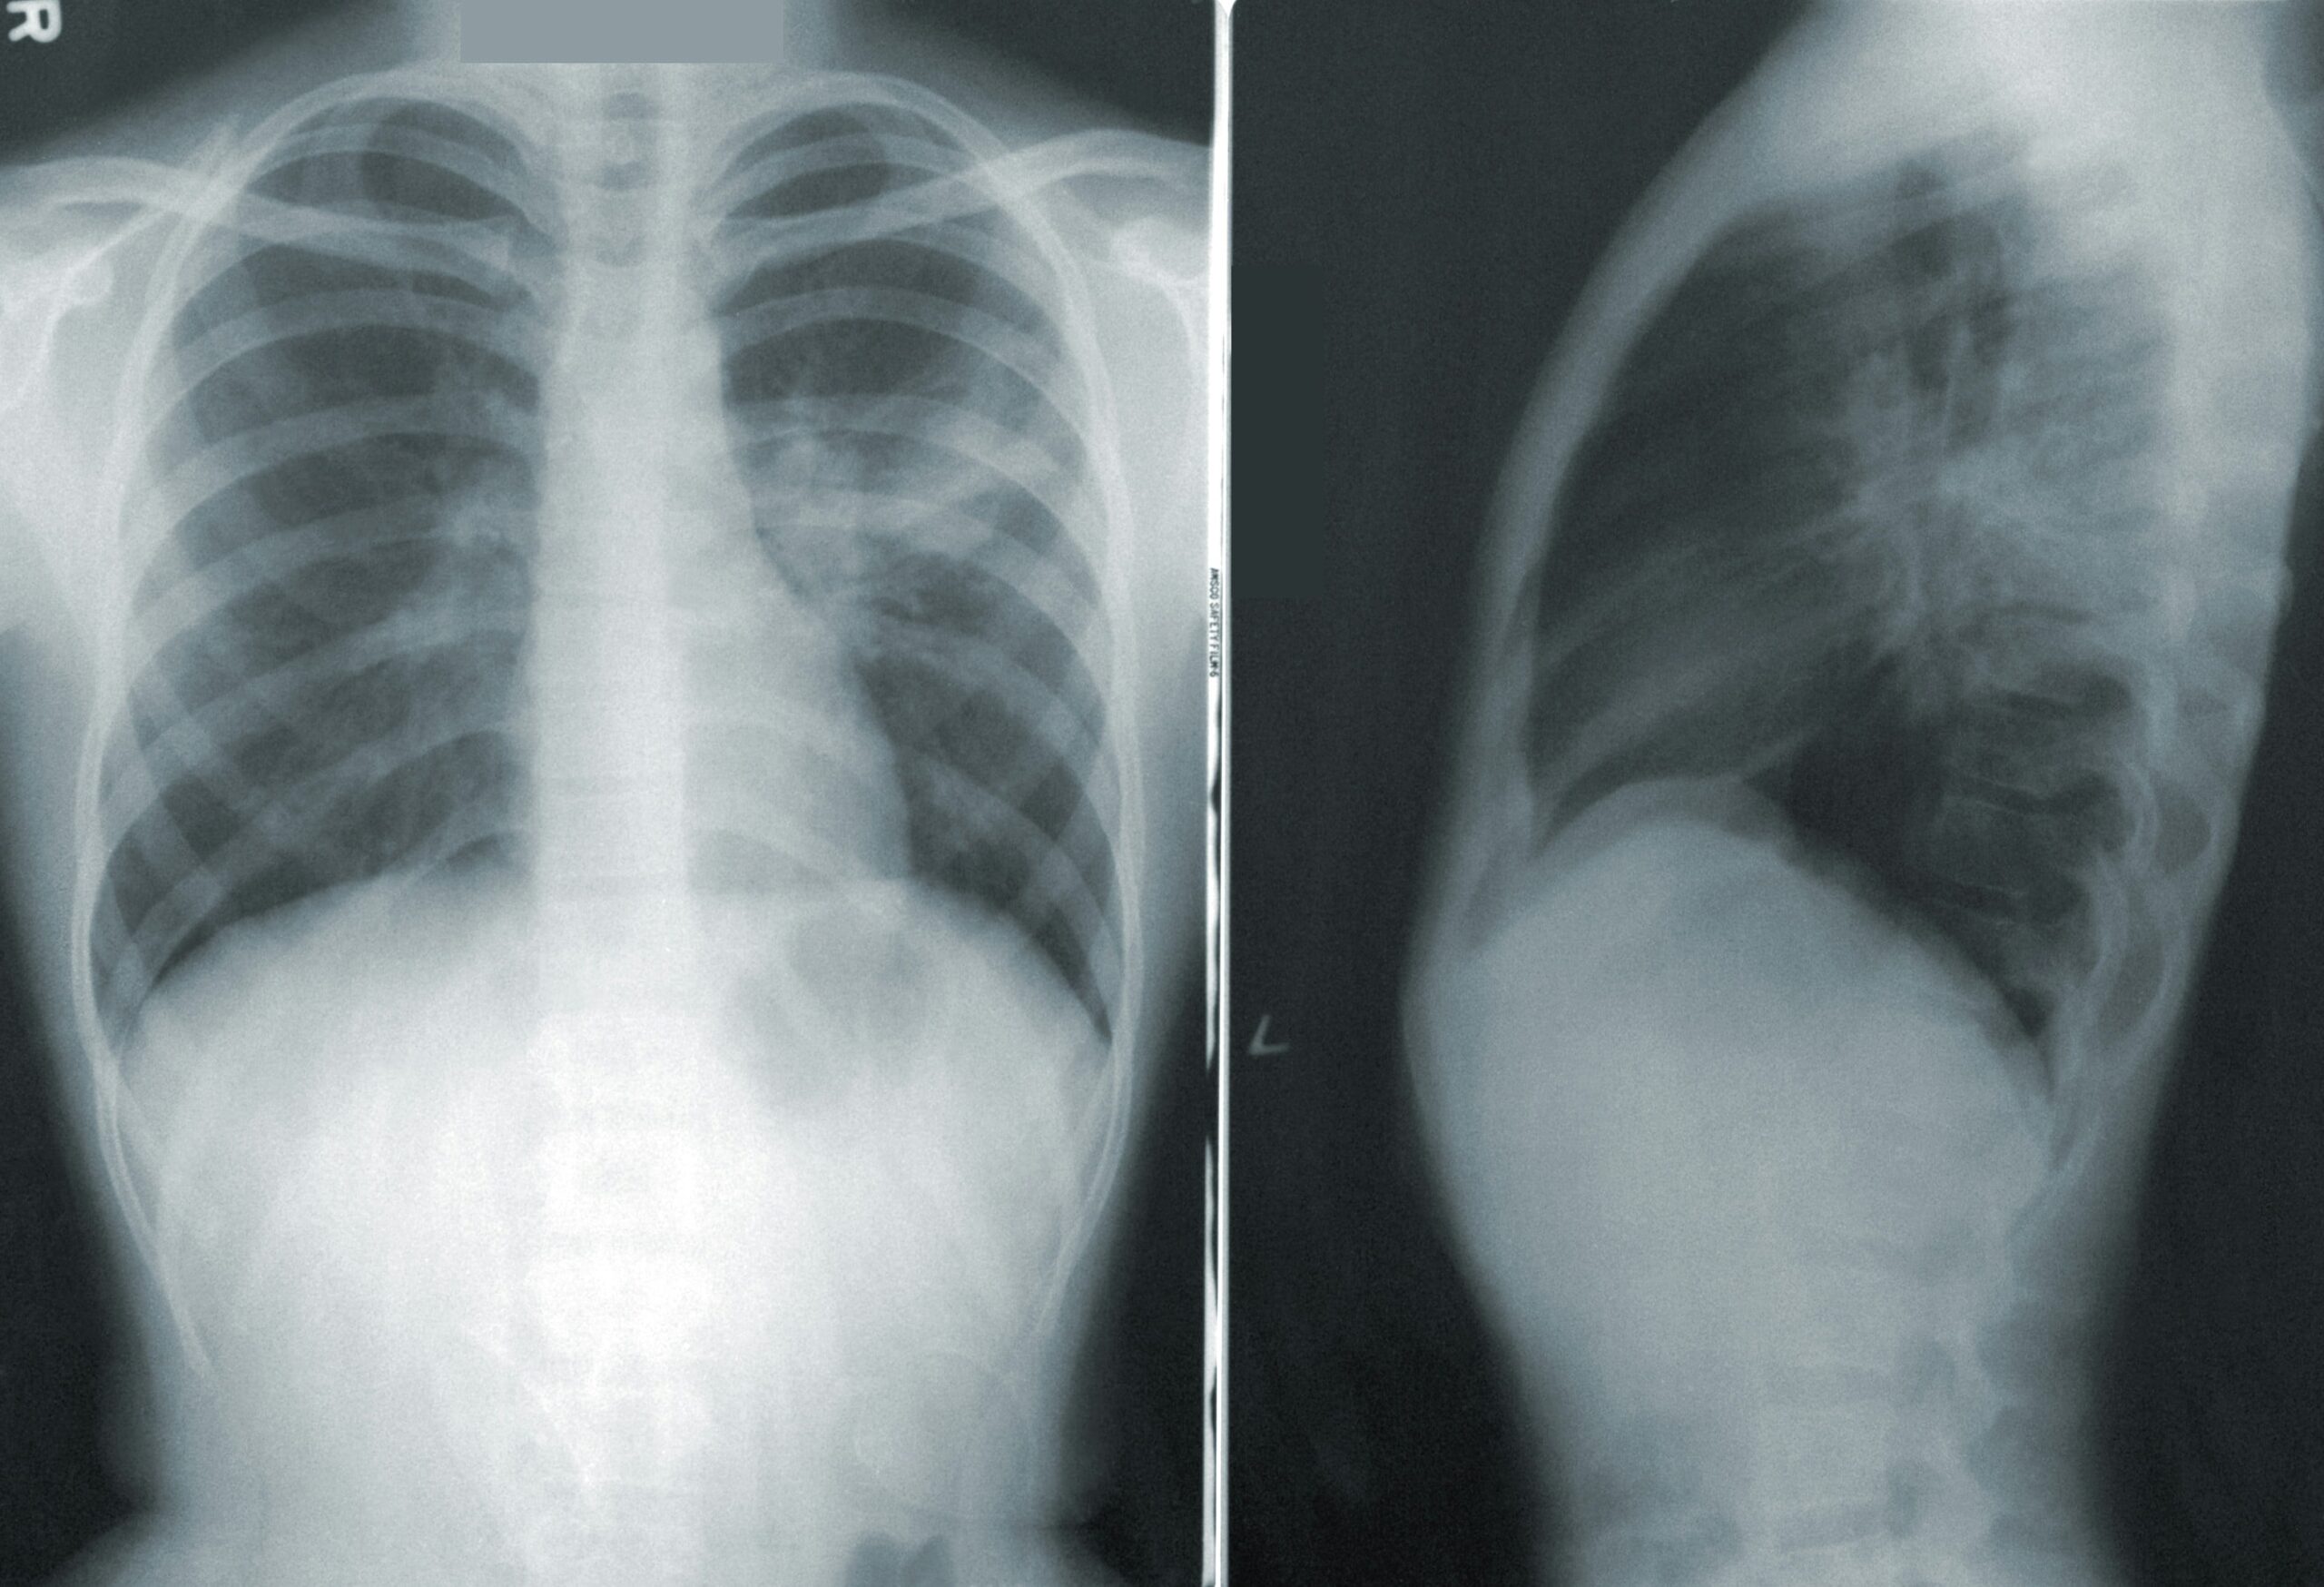

X-rays are used much less now in the diagnosis of back pain, and are commonly not recommended or even allowed to be taken unless there are clear signs that they are indicated with good medical reasons. Chiropractors used to take X-rays more routinely and some still do to show the structure of the spine and the extent and location of any wear and tear or degeneration, which can be helpful in pin-pointing the source of the underlying causes of back pain. The medical profession takes the view that unless the patient is suffering, in pain, with a clear need for X-ray, then they are not generally necessary in back pain diagnosis, often because osteoarthritis or wear and tear is almost universal and doesn’t really affect the treatment.

X-rays may well be indicated for:

- Severe trauma or possible fractures

- Hip osteoarthritis or wear and tear

- Bone tumours

- Osteoporosis (alongside bone density scans)

- Severe chronic long-term spinal pain that is not settling.

- Medical ‘Red-flags’, possibly with night or deep bone pain

- Suspicion of other arthritic or joint diseases

- Spinal surgeons will now use X-rays alongside MRI scans to help build a full picture of a patient’s spine before considering surgery.

X-ray picture and symptoms commonly don’t match

It’s very common that the X-ray picture and a patient’s symptoms don’t match. Sometimes the patient is in severe debilitating pain, yet their X-ray picture is ‘normal’ and at other times their X-rays may show severe wear and tear and leaving the practitioner to wonder how they are even able to stay active, yet the client is happily carrying on with life!